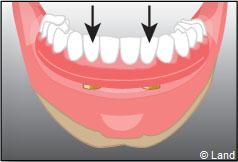

Les implants peuvent aussi servir à stabiliser un appareil amovible au maxillaire supérieur comme au maxillaire inférieur. Dans ce cas, les implants retiennent la prothèse amovible par des systèmes d’attachement.

Deux techniques sont possibles. Elles font appel à la barre de rétention ou aux boutons-pressions.

Situation clinique initiale

Situation clinique terminée